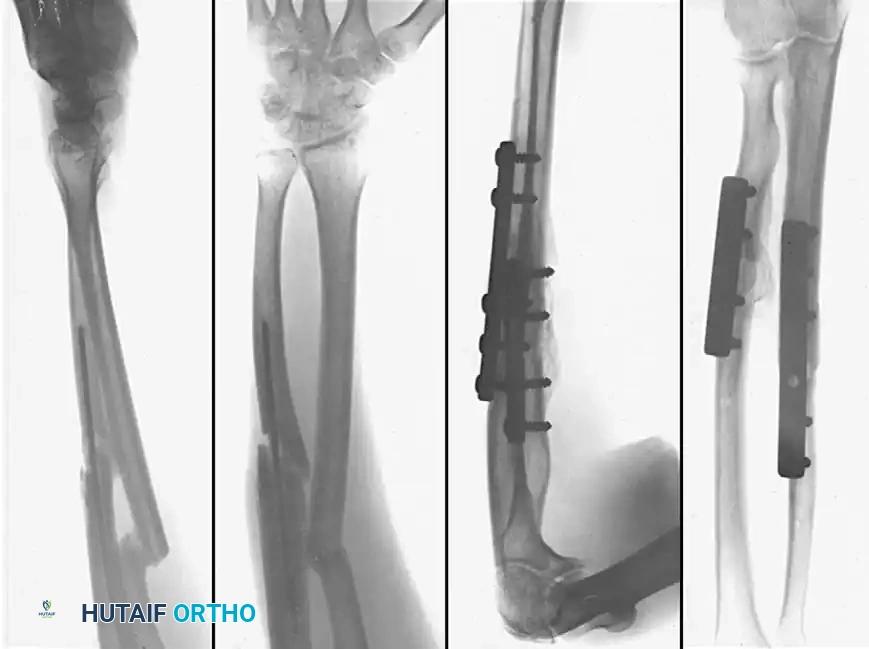

Diaphyseal malunion of the radius and ulna treated with corrective osteotomies and rigid internal fixation using dynamic compression plates.

* Preoperative Templating: Contralateral normal forearm radiographs are essential to template the exact location and magnitude of the normal radial bow.

* Approach: The radius is typically approached via a volar (Henry) approach to allow for optimal plate placement on the flat tension surface, while the ulna is approached directly over its subcutaneous border.

* Fixation: Following corrective osteotomy (often requiring a structural tricortical iliac crest bone graft to restore length and correct angular deformity), rigid fixation with 3.5 mm limited contact dynamic compression plates (LC-DCP) or locking compression plates (LCP) is mandatory. At least six cortices of fixation (three screws) are required proximal and distal to the osteotomy site on both bones.